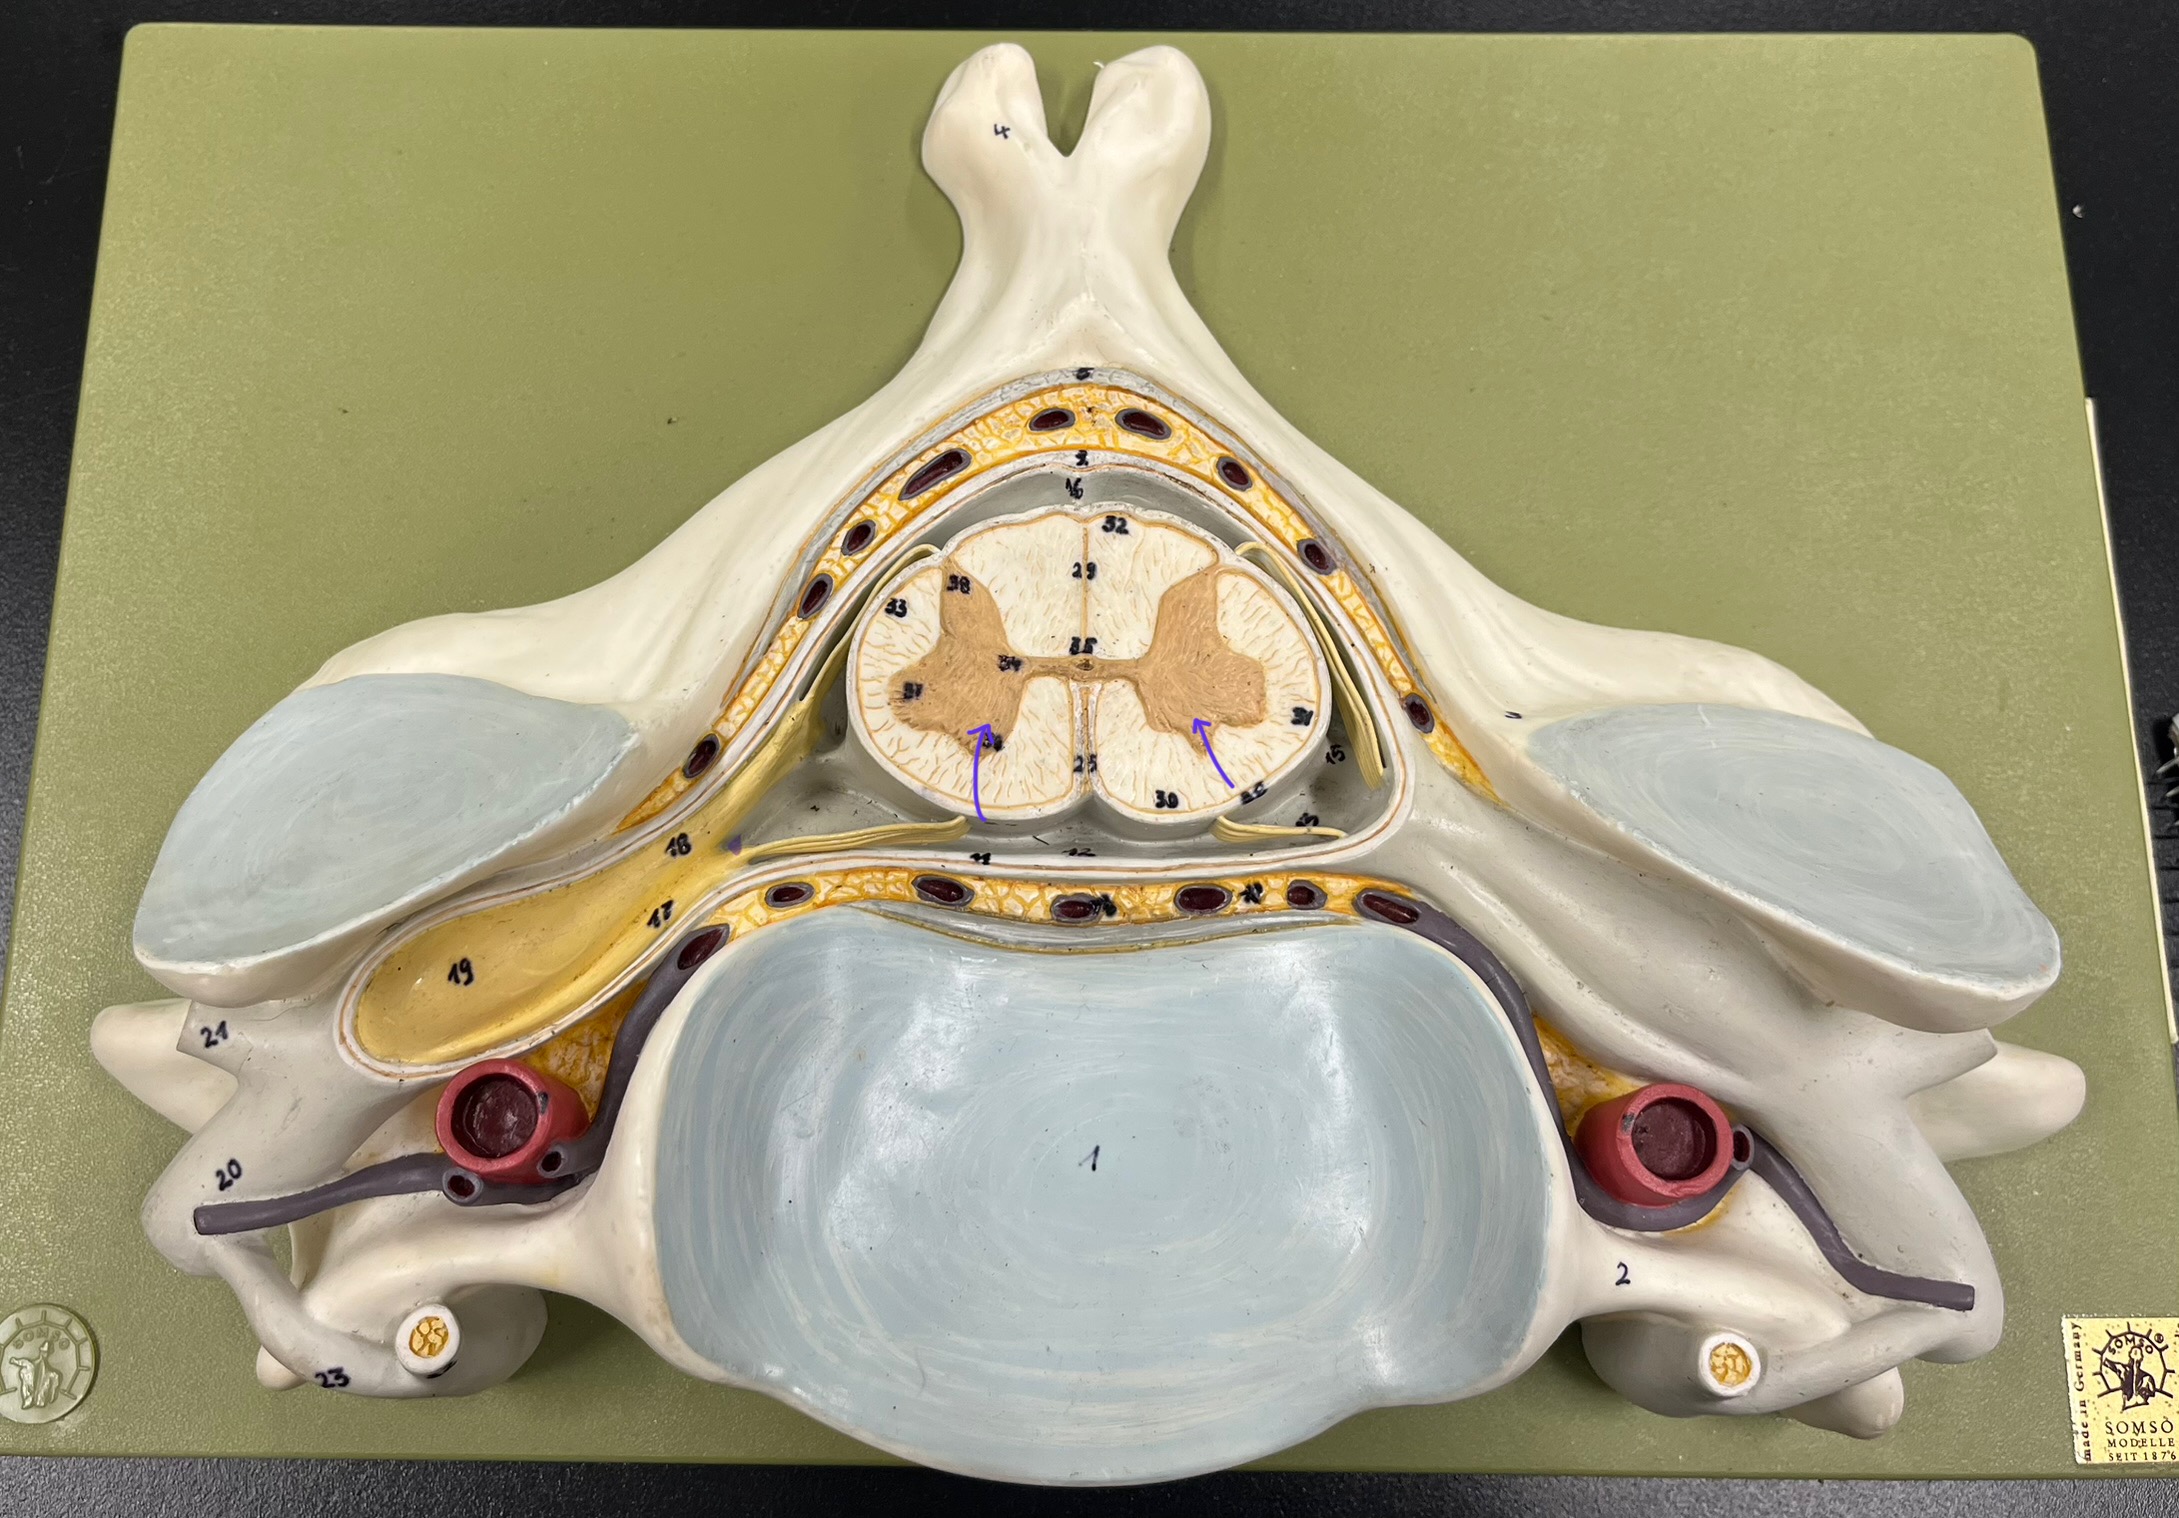

epidural space

dura mater

subdural space

arachnoid mater

subarachnoid space

pia mater

denticulate ligaments

What is the groove here?

anterior median fissure

posterior median sulcus

posterior (dorsal) horn

posterior (dorsal) horn; R—>L

anterior (ventral) horn

lateral horn (selected models)

gray commissure

central canal

anterior column

lateral column

posterior column

white commissure

posterior (dorsal) root ganglion

What is the bulb here?

posterior (dorsal) root ganglion

posterior (dorsal) root

posterior (dorsal) root

anterior (ventral) root

anterior (ventral) root

dorsal ramus

dorsal ramus

ventral ramus

ventral ramus

rami communicantes

rami communicantes

sympathetic chain ganglia

sympathetic chain ganglia